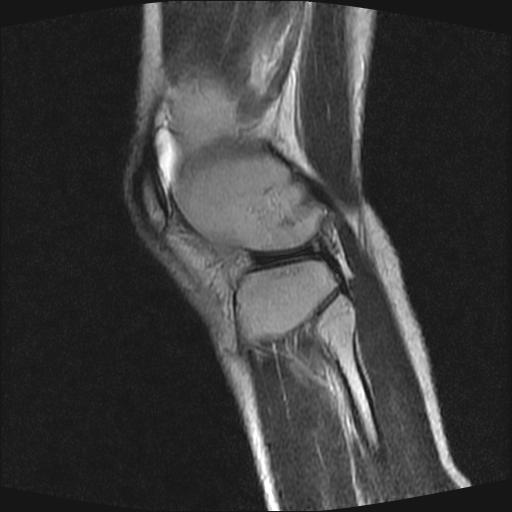

标题: MRI1265:男性40岁,右膝关节 [打印本页]

标题: MRI1265:男性40岁,右膝关节

40岁男性,右膝关节外伤,x光平片示,髁间隆突撕脱骨折。

1、前交叉韧带撕裂;

2、外侧半月板后角撕裂;

3、关节腔积液。

前交叉韧带撕裂,关节腔积液.

半月板1-2级损伤   前交叉韧带撕裂伤   关节腔少量积液  诸骨未见新鲜外伤性改变

髁间隆突撕脱骨折;内侧副韧带损伤。

内侧副韧带撕裂及关节腔积液是肯定的,但是前交叉撕裂确定吗?会不会有容积效应的因素,因为前一张前交叉显示清楚,连续性良好,且较光滑。请问楼主有关节镜支持吗?我们医院也经常有这样的患者,但苦于没有关节镜,而无法对照、证实(除非完全断裂),出现了不同的诊断结果只能毫无意义的争论。

1、前交叉韧、内侧副韧带撕裂;

3、关节腔积液。4、髁间脊撕脱骨折。

除了关节积液外并无韧带撕裂,acl胫侧附着点有2束,正常情况下脂肪信号。此病例应加做压脂像以便观察是否有骨损伤。